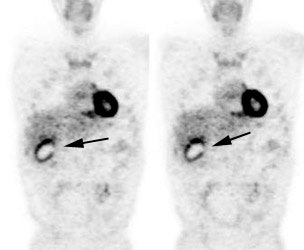

|

Benign adrenal lesion with FDG uptake: The patient shown below had a left adrenal mass which had remained stable for 2 years (white arrow). The stability over time and CT features would be consistent with a benign adrenal lesion- likely an adenoma. Note the marked FDG uptake within the mass on PET imaging (black arrows). Benign adrenal adenomas can accumulate FDG resulting in false positive exams. The use of PET/CT has been shown to improve the specificity of the PET exam. |